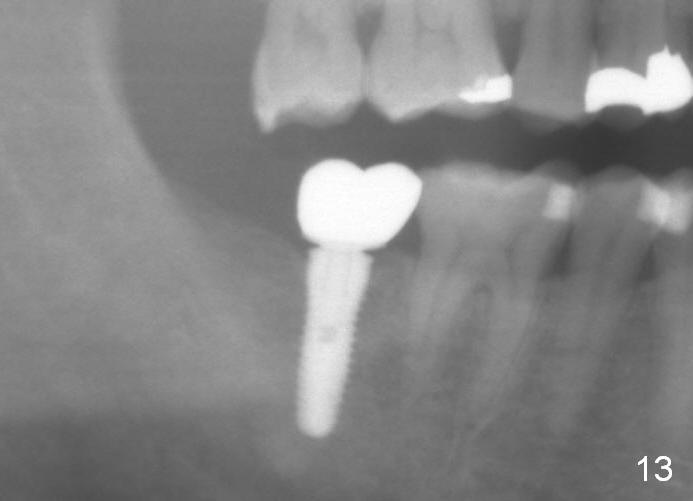

The wound heals uneventfully (Fig.8,9: taken 3 months postop). When an abutment is placed, there is no clearance for a crown. Two mini-implants are placed for the tooth #2 intrusion (Fig.10,11). Four months later, segmental orthodontic appliance is added because of lack of result of intrusion and buccoversion of the tooth #2 (Fig.12). Two months later, all of orthodontic treatment is terminated at the request of the patient. After heavy reduction of the tooth #2, a crown is cemented. Fig.13 (panoramic X-ray) is taken 11 months post cementation. There is no bone loss nearly 3 years post cementation (Fig.14).